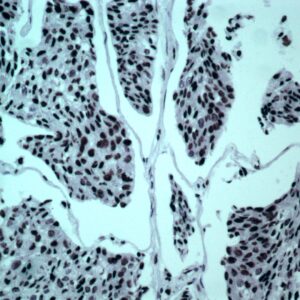

BioGenex has pioneered the development of miRNA research and diagnostics tools with leading-edge products. Currently, we offer over 240 ready-to-use (RTU) Super Sensitive™ Nucleic Acid (SSNA) miRNA ISH probes for accurate and early tumor diagnosis. These probes are sensitive enough to detect low-abundant miRNA(s) that are often required to identify biomarkers. They have a high melting temperature enabling stringent washes to remove non-specific binding. BioGenex miRNA probes are dual-end labeled with an anti-fluorophore to amplify the signal and yield clean and intense staining.